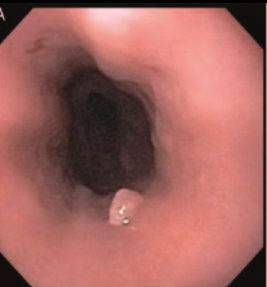

Endoscopic Appearance of an Esophageal Squamous Papilloma in a Pediatric Patient